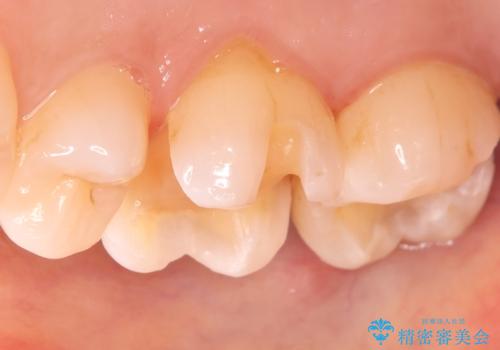

- 昔入れた金属の被せ物を白い物に変えたいと思い来院された患者様です。レントゲン等確認し審美的によく、強度のあるセラミックインレーにて治療いたしました。

審美的に良い補綴物に変わり満足いただきました。かみ合わせも問題なく快適に食事できているとのことでした。